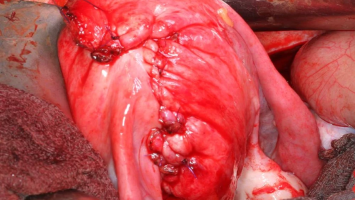

Adenomyose und Kinderwunsch – wenn die Hysterektomie keine Option ist

Von chronischen Schmerzen bis hin zu Blutungsstörungen: Nicht selten führt eine Adenomyose zu einer Hysterektomie. Doch was, wenn ein Kinderwunsch besteht? Neue Erkenntnisse zeigen, dass eine fertilitätserhaltende Operation eine vielversprechende Alternative sein könnte.

Operative Konzepte für die Therapie der Endometriose

Die operative Therapie der Endometriose ist anspruchsvoll. Sie reicht von der Resektion oberflächlicher peritonealer Herde bis zur interdisziplinären Operation mit partiellen Organresektionen an Darm, Blase, Urogenitaltrakt und Zwerchfell. Die …